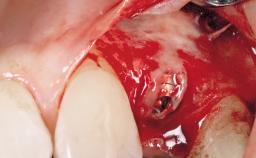

Late Placement of an Implant in a Maxillary Left Central Incisor Site

A 36-year-old female patient was referred for the replacement of the upper left central incisor (tooth 21), which had fractured. Although the tooth had been asymptomatic for many years, the crown began to loosen, at which time she presented to her dentist for an assessment. Teeth 21 and 22 had both been endodontically treated many years previously. She was a healthy individual and a non-smoker.

The crown of tooth 21 was splinted to the adjacent teeth with composite resin, and the gingiva was inflamed.

Bone Volume Deficient horizontally, requiring prior grafting